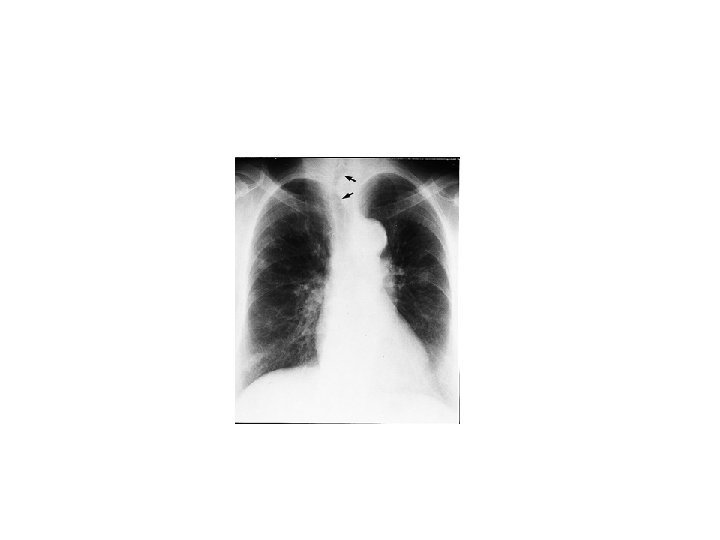

Palpation Trachea 4 -5 cm of the upper trachea can be felt in the neck between the cricoid cartilage and the sternal notch. § Pushed –pneumothorax -pleural effusion § Pulled—fibrosis --collapse

§ Chest expansion– normal up to 5 cm -abnormal < 2 cm § Apex beat § Tactile fremitus --Ask the patient to say 99 --you should feel the vibration transmitted through the airways to the lung.

§ Increased in---pneumothorax --emphysema § Decreased---pleural effusion Auscultation Breath sounds— § Vesicular—normal --insp. twice that of expiration --no pause § Bronchial –inspiration is shorter than expiration ---gap between insp. and exp.